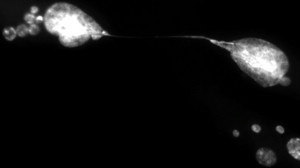

“Genetically, we were able to reproduce the phenomenon of cellular aging in the laboratory and ensured that all the telomeres of a population of cells became dysfunctional,” said PhD student Marc-Alexandre Olivier, co-first author of the study with former colleague Sabrina Ghadaouia, currently pursuing postdoctoral studies in England. “With our equipment, we then observed in real time what was happening inside each single cell.”